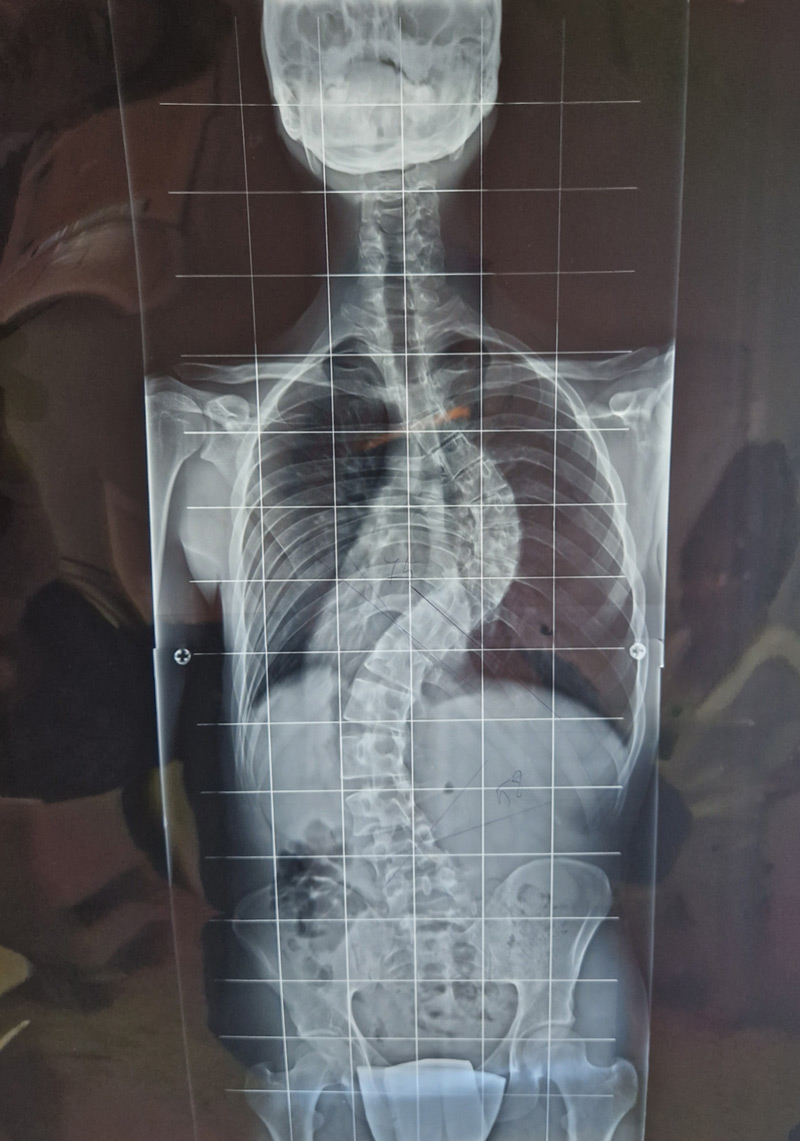

DIAGNOSI:

Scoliosi dorso lombare

Radiografia della colonna in toto pre-operatoria